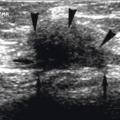

L’échographie pariétale est privi- légiée ; elle permet de localiser, me- surer et suspecter le nodule endo- métriosique dans la cicatrice de césarienne mais aussi de confirmer dans certaines situations les diagnostics différentiels. Il est conseillé, au mieux, de faire une échographie en crise pendant les règles et une en dehors des règles pour mettre en évidence le caractère fluctuant du nodule.27,29 Cependant, une échographie en dehors des règles retrouve déjà une image assez typique (fig. 1).